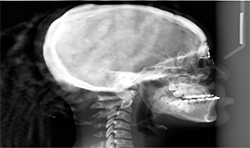

Panoramic and cephalometric radiographs are of limited use due to superimposition of anatomical structures (Figs. 5A, 5B, 5C).

The Planmeca Viso G7 CBCT unit and Planmeca Romexis software can stitch two volume scans automatically with one click. The top portion of the skull (Fig. 7A) and the remaining maxillofacial portion (Fig. 6) were stitched to make a single skull volume (Fig. 7B). Multidisciplinary team has been working on this patient. Prosthodontics and oral surgery will plan to manage maxillary alveolar cleft and associated malocclusion following the CBCT images.